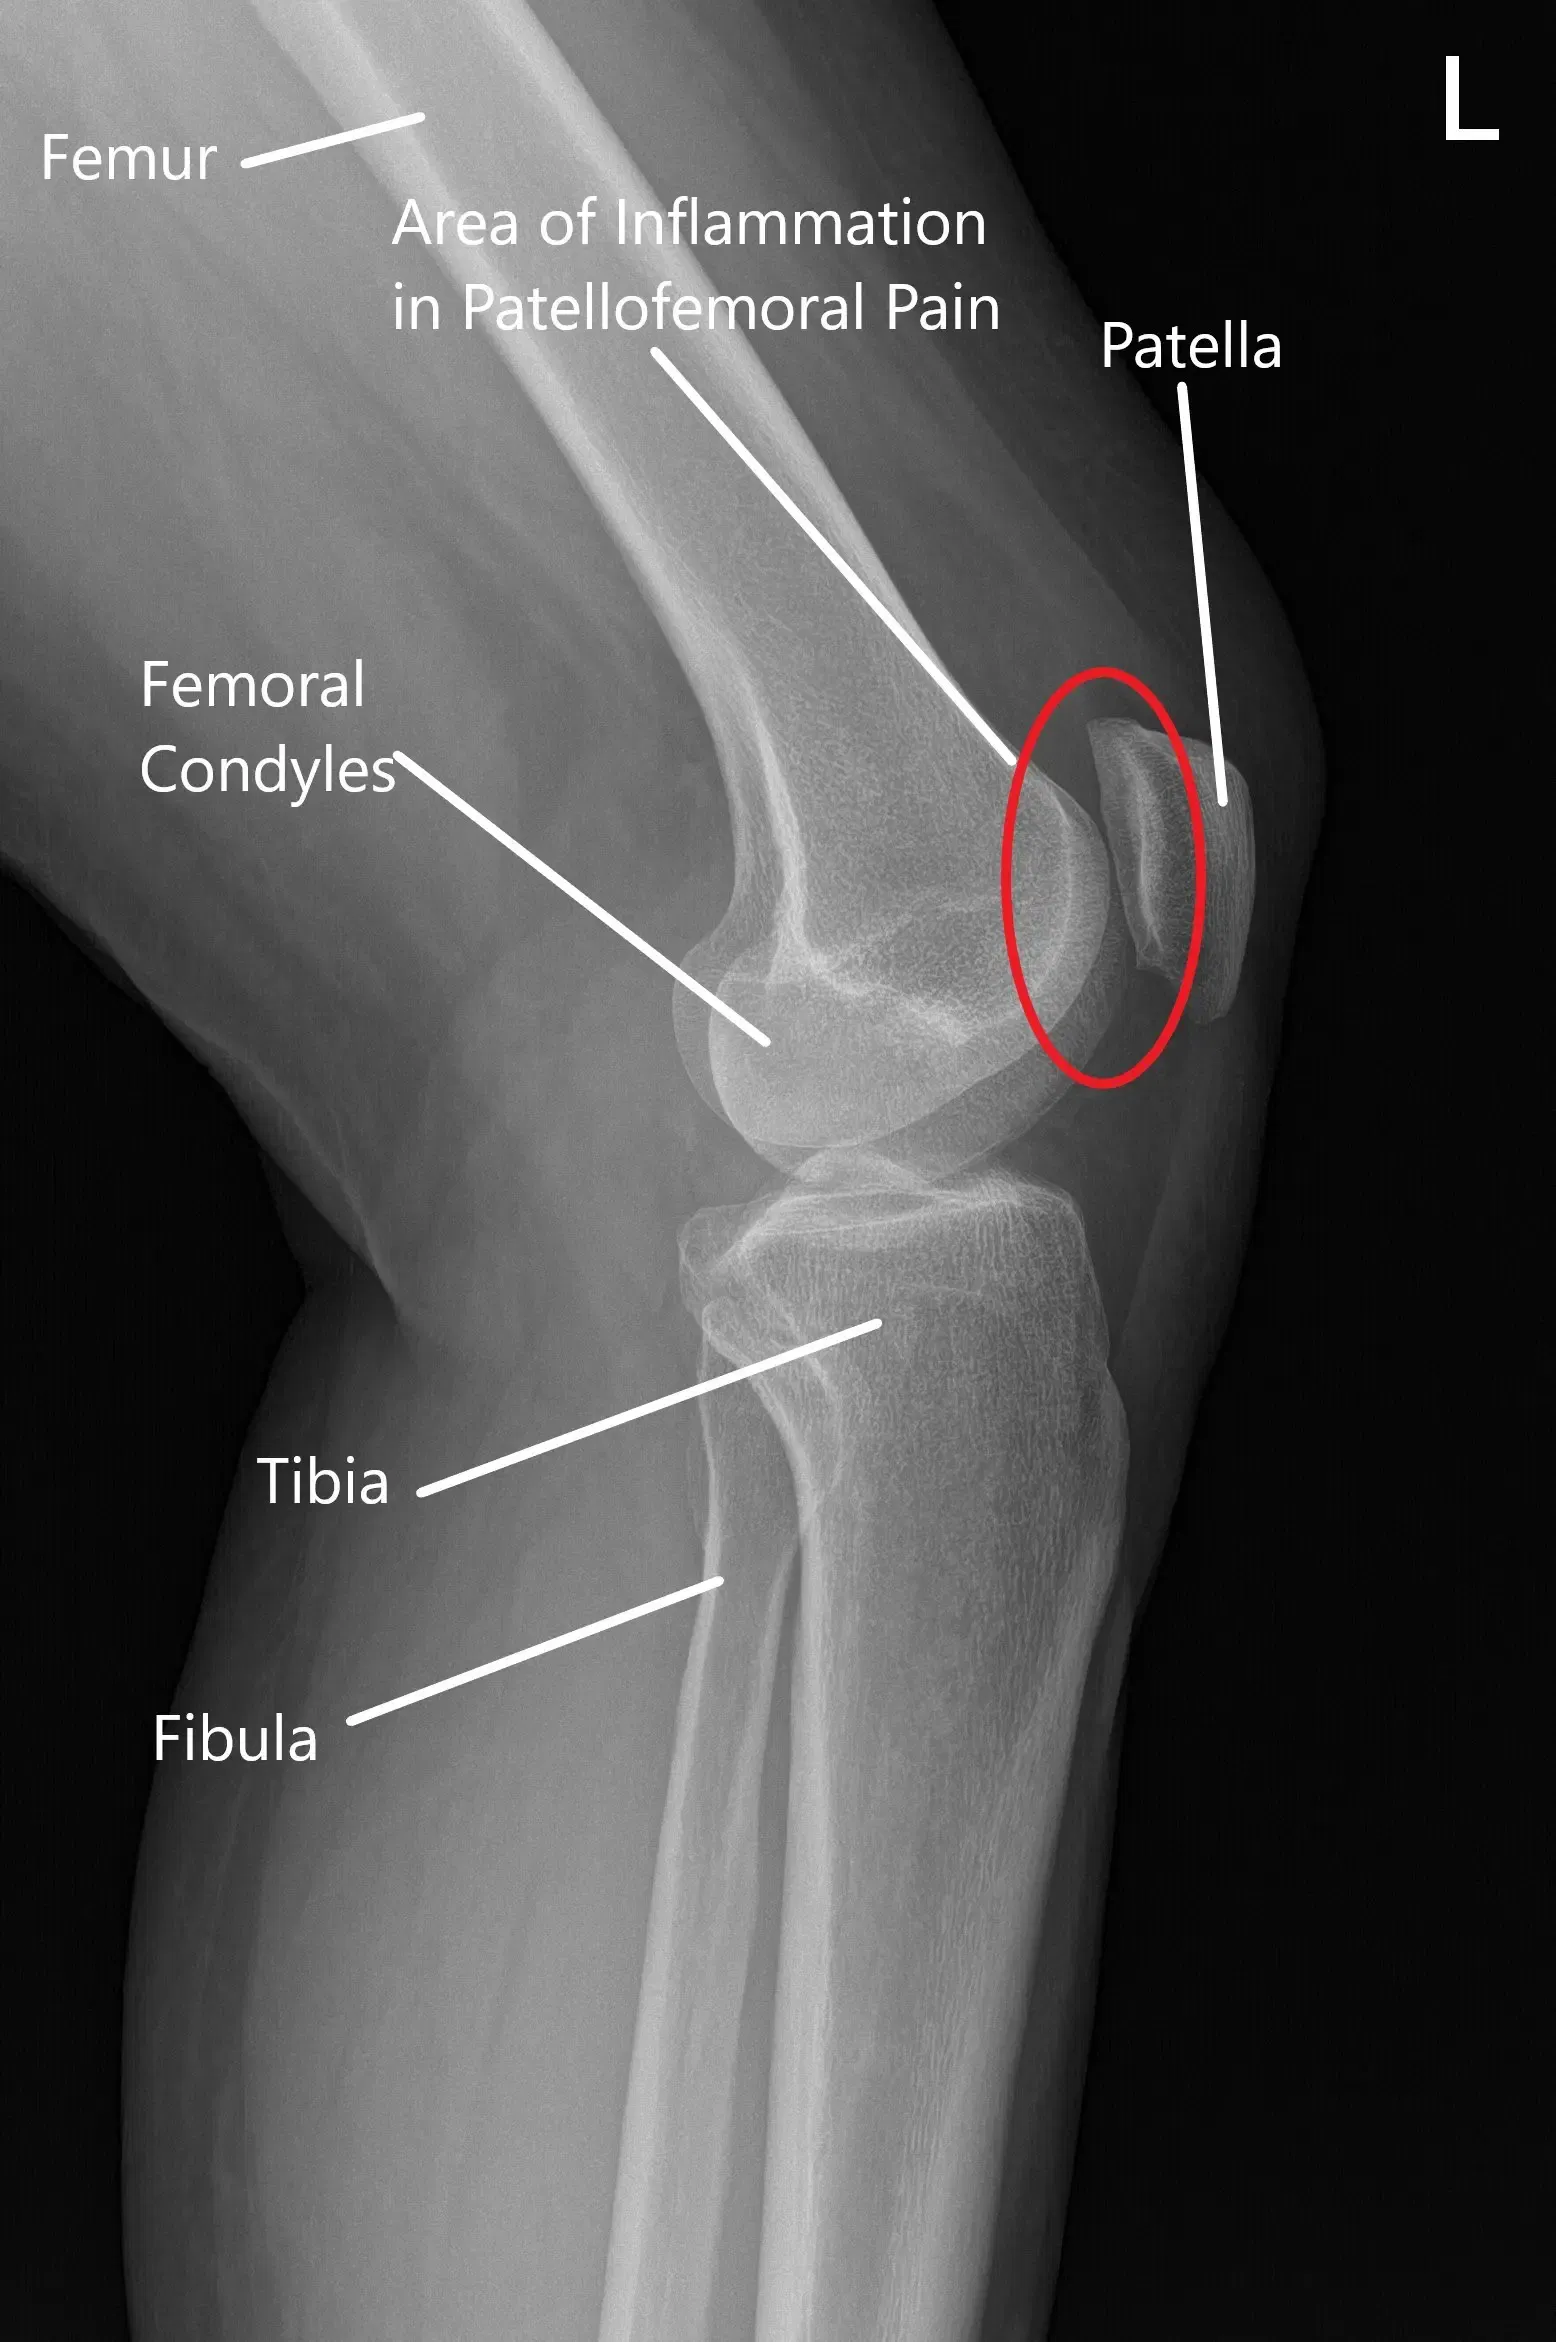

La articulación patelofemoral es donde la rótula (rótula) descansa dentro de la ranura del fémur (hueso del muslo). La articulación de la rodilla funciona permitiendo movimientos suaves de flexión y estiramiento, ayudando la rótula a estabilizar y guiar estos movimientos. En la SDFP, la alineación de la rótula se ve comprometida, a menudo debido a desequilibrios musculares, ligamentos tensos o un mal entrenamiento, lo que provoca dolor y molestias.

Radiografía normal de la articulación de la rodilla que muestra las distintas estructuras en la vista anteroposterior y lateral.